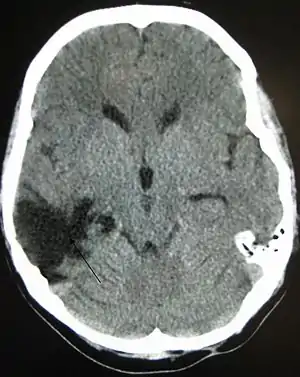

| تصویر سیتی از یک سر که چندین سال پیش دچار ضربه مغزی شدهاست و نشاندهنده یک فضای خالی در جایی که ضربه خوردهاست، میباشد. |

یک گروه متداول با بیشترین آسیبدیدگی، ضربه مغزی (TBI) است که ضربه فیزیکی یا آسیب دیدگی سر از یک منبع خارجی پس از آن قرار دارند و اصطلاح آسیب مغزی اکتسابی (ABI) در محافل مرتبط برای تمایز میان آسیبهای مغزی پس از تولد با اختلالهای ژنتیکی و مادرزادی استفاده مب شود.[1] آسیبهای اولیه و ثانویه مغز فرایندهای درگیر را شناسایی میکنند، در حالی که آسیب کانونی و منتشر مغز شدت و محل را توصیف میکند.